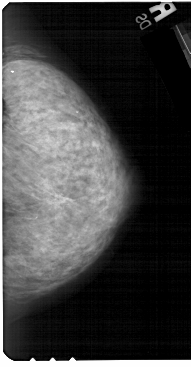

A_1325_1.RIGHT_MLO

RIGHT_CC LINES 5491 PIXELS_PER_LINE 2851 BITS_PER_PIXEL 12 RESOLUTION 43.5 NON_OVERLAY

RIGHT_MLO LINES 5491 PIXELS_PER_LINE 2986 BITS_PER_PIXEL 12 RESOLUTION 43.5 NON_OVERLAY